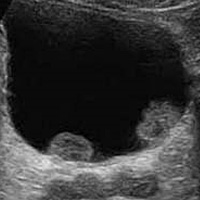

Το πρώτο διαγνωστικό εργαλείο είναι το υπερηχογράφημα νεφρών κύστεως (και προστάτη για τους άνδρες), όπου συνήθως εμφανίζονται ένα η περισσότερα θηλώματα.